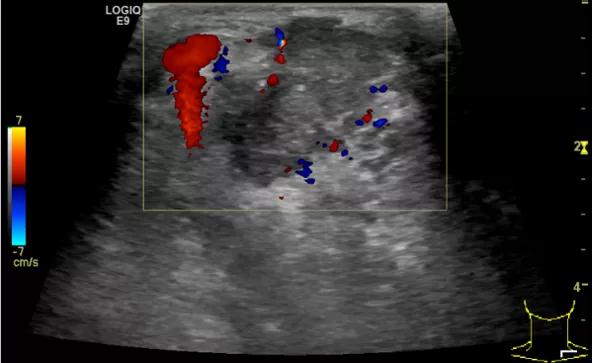

第四例是胸腺癌化妆包,术后、化疗之后淋巴结转移,肿块范围巨大,99mm*61mm,边界不清,呈浸润状,肿块包绕颈动脉,颈内静脉压闭,症状明显。由于患者放化疗也不敏感、血供非常丰富,于是采取多点姑息性消融。姑息性消融后未实现完全消融,病灶大片坏死,肿胀疼痛得到明显的缓解,后续患者未再来复查。

(病例4图例)